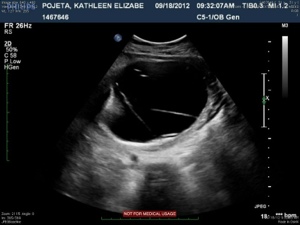

The next four images just show various views of the strands/septations that are visible within the sac.

20120921-213515.jpg